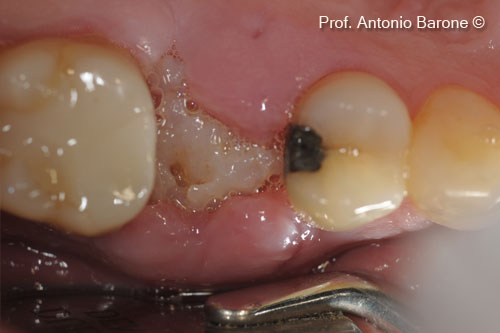

Một bệnh nhân nữ (54 tuổi) cho thấy răng bị gãy ở vị trí số 15.

Hình ảnh lâm sàng mặt nhai của một chiếc răng bị gẫy

Hình ảnh lâm sàng từ phía má của một chiếc răng bị gẫy